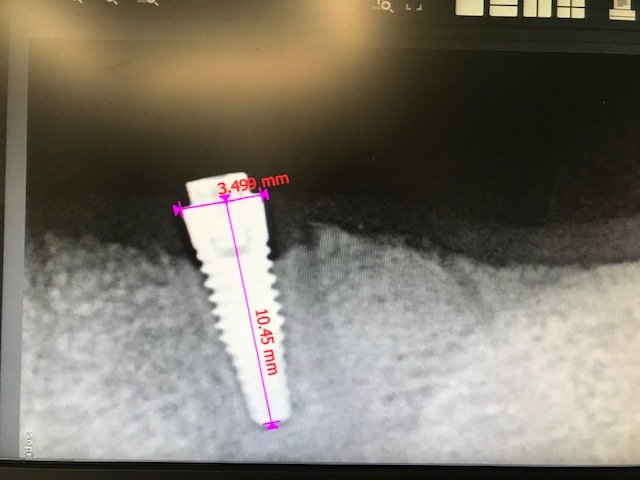

Implante #35

Buenos días, me gustaría confirmar si el implante que os presento es un Phibo TSA RP y, si no es así, qué implante debe ser. se colocó hace más de [...]